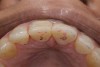

Fig 3. Preoperative view showing erosion of palatal surfaces of upper anteriors.

Figure 3

A 40-year-old female patient complained of short teeth and asked for various options to improve her smile. On clinical examination, the palatal surfaces of the maxillary anterior teeth were found to be eroded, with the residual tooth structure having a smooth and shiny appearance (Figure 1 through Figure 3). In MIP, no restorative space was available, as the lower anterior teeth fit tightly into the upper palatal surfaces, making this a clinically challenging situation to treat conservatively. In most cases of conventional treatment protocols, such upper teeth are devitalized and restored with crowns that structurally leave the teeth in a compromised condition.10